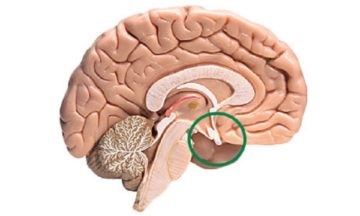

Ahol van. Nem található körülbelül a közepén a koponya alján az agy felületén. Ezen a ponton az alapja a koponyacsontok is egy speciális mélyedés, ez az úgynevezett török nyereg.